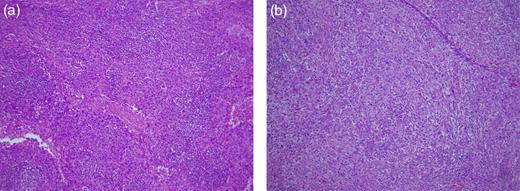

There was no evidence of tumor in the submandibular gland. Histological examination showed poorly differentiated SCC in the lymph nodes located at Level II (Fig. 1a). The patient was considered to have a carcinoma of unknown primary site because no primary lesions were found on detailed examinations of the esophagus, lung, uterine cervix and skin. A preoperative computed tomographic (CT) scan showed a small lesion with contrast effect in the transverse colon, which was difficult to distinguish from inflammation. Three months after operation, it was noted that the colonic lesion had grown considerably (Fig. 2). Fluorine-18 fluorodeoxyglucose positron emission tomography showed abnormal uptake in the transverse colon, but there was no accumulation at other sites (Fig. 3).

(a) Cervical lymph nodes. The specimen shows poorly differentiated SCC (H&E stain, ×40). (b) Metastatic colorectal tumor. The specimen shows poorly differentiated SCC similar to that seen in the cervical lymph nodes (H&E stain, ×40).

Colonoscopy revealed a 40-mm submucosal tumor with an inflamed surface in the transverse colon. The appearance of this lesion suggested a metastatic lesion from another site, and biopsy was performed, but did not provide a definitive diagnosis (Fig. 4). Laparoscopic right hemicolectomy was then performed. Histological examination of the resected specimen showed features of poorly differentiated SCC, similar to that previously seen in the cervical lymph nodes (Fig. 1b). There were no elevations of serum tumor markers. The patient was discharged 11 days after surgery without any complications. No further adjuvant treatment was given because of her poor general condition.